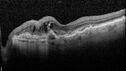

Central Retinal Vein Occlusion with cilioretinal artery occlusion72 views63 year old female who lost vision in the left eye 2 days ago. She was in the emergency room and had a lot of tests done which were all reportedly normal. The right eye is OK.

VA OD: Dcc20/25 NccJ2

VA OS: Dcc20/200-1 PHNI Ncc20/400-1

IOP: TP: OD:11 OS:12